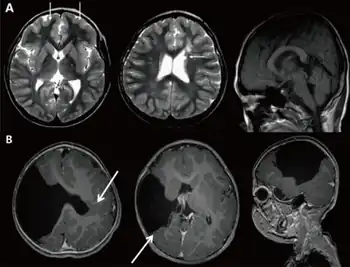

a) Brain magnetic resonance imaging with global developmental delay (and increased serum creatine kinase) b) global developmental delay (and left hemiplegia )

• Targeted MRI brain can be considered second line in selected patients, and is more likely to contribute to a diagnosis if the child has abnormal physical signs such as microcephaly, macrocephaly, a change in head circumference, focal neurological signs, or epilepsy.